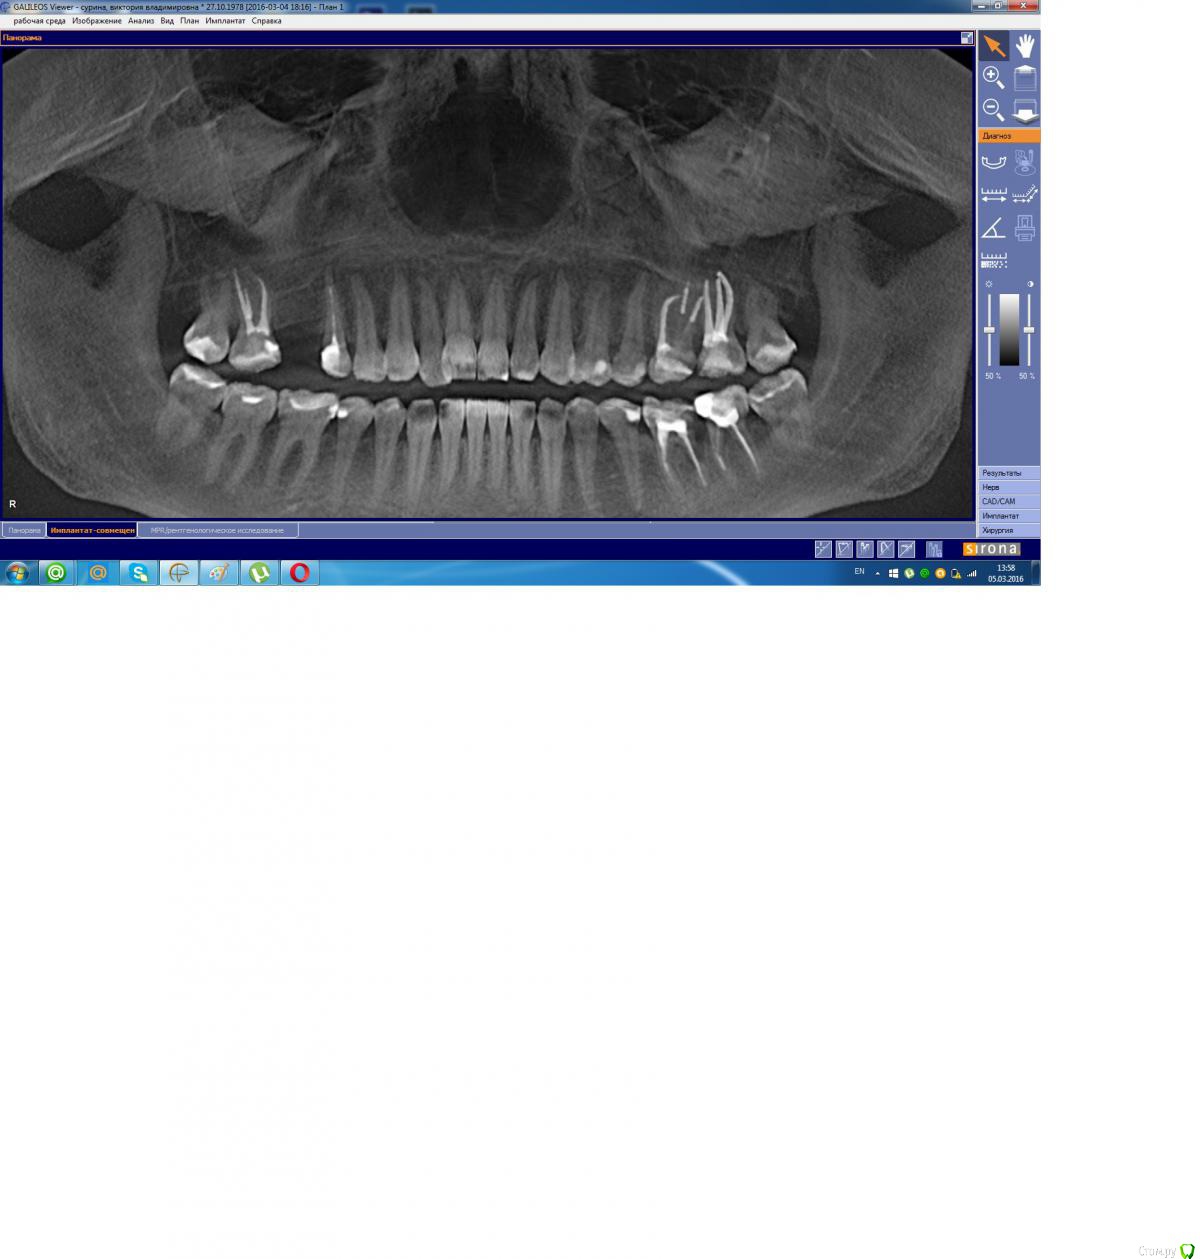

Scorpio Опубликовано 5 марта, 2016 Поделиться Опубликовано 5 марта, 2016 (изменено) Здравствуйте. 3 дня назад под нижней шестеркой образовался абсцесс, боли нет или очень слабая иногда. Вчера обратилась к доктору, сказали удалять зуб. Я отказалась, доктор посоветовала пить антибиотики и полоскать Можно ли сохранить зуб, не удаляя?Снимок прилагаю, если надо, есть КТ.И еще, если возможно по снимку определить, подскажите с какими зубами еще есть проблемы? Изменено 5 марта, 2016 пользователем Scorpio Ссылка на комментарий

Doctor Vlad Опубликовано 5 марта, 2016 Поделиться Опубликовано 5 марта, 2016 док прав. проблемных зубов много... 7ка рядом .. передние зубы внизу... все лечить. 8ки сразу удалять Ссылка на комментарий

Scorpio Опубликовано 7 марта, 2016 Автор Поделиться Опубликовано 7 марта, 2016 Спасибо за ответы. Сегодня иду удалять, хотя отек почти спал, зуб стоит как влитой, вообще не беспокоит, не болит ничего.А верхняя шестерка "распирает" и ее даже слегка можно пошатать пальцами, неужели, это тоже кандидат на удаление в будущем? Обидно, только пролечила все эти зубы в прошлом-позапрошлом году. Но есть один влияющий фактор- грудной ребенок, закончила кормить только в декабре. Ссылка на комментарий

Scorpio Опубликовано 7 марта, 2016 Автор Поделиться Опубликовано 7 марта, 2016 Сейчас почитала про симптомы про 26 , похоже на периодонтит. Зуб лечила год назад. В хорошей клинике, отдала кучу денег. Скажите, могут быть претензии к лечению или это чисто проблемы организма? Ссылка на комментарий

dok1 Опубликовано 7 марта, 2016 Поделиться Опубликовано 7 марта, 2016 Да лечение у вас как раз на достаточно хорошем уровне. Там между зубами карман образовался. Процесс необратимый. Потеря зубов неизбежна. Но чем дольше сохраняете зубы - тем болше кости теряется вокруг них. Ссылка на комментарий

Zlata-doctor Опубликовано 7 марта, 2016 Поделиться Опубликовано 7 марта, 2016 нижний точно на удаление. Все остальное надо смотреть на месте. Я бы не была столь категорична в отношении 25-26. 1 Ссылка на комментарий

red_butler Опубликовано 7 марта, 2016 Поделиться Опубликовано 7 марта, 2016 А верхняя шестерка "распирает" и ее даже слегка можно пошатать пальцами, неужели, это тоже кандидат на удаление в будущем? с верхом на снимке проблем не увидел, лечение выполнено на высоком уровне. Но 2.6 2.7 нужно обязательно протезировать Ссылка на комментарий